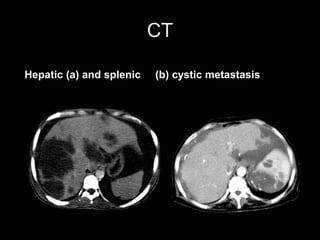

Hepatic (a) and splenic (b) cystic metastasis

CT Hepatic (a) andsplenic (b) cystic metastasis